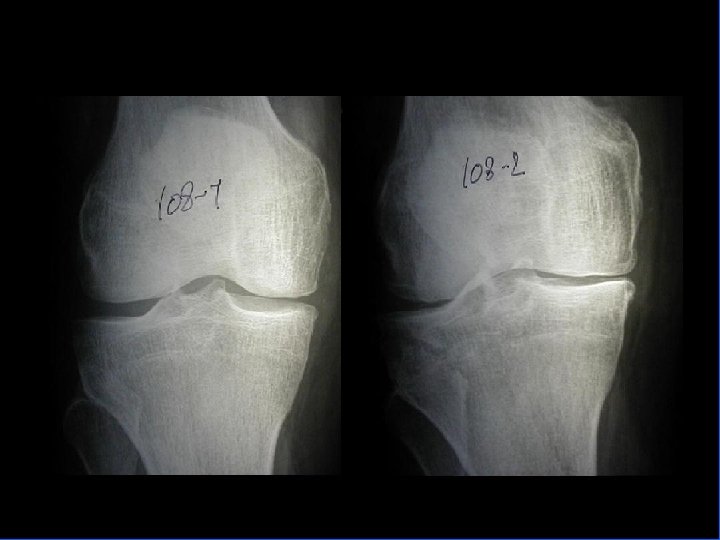

Arthrose fémoro-tibiale Iconographie • Radiographie : – Face en appui bipodal – Profil – Schuss (face en charge à 30° de flexion) pour compartiment post • Signes: – Pincement interligne – Ostéophytose – Ostéosclérose sous-chondrale avec géodes

Arthrose fémoro-tibiale Pronostic • Évolution très variable • Pas de facteurs pronostique bien individualisé mais semble que – obésité – antécédents traumatiques = Facteurs d’évolutivité